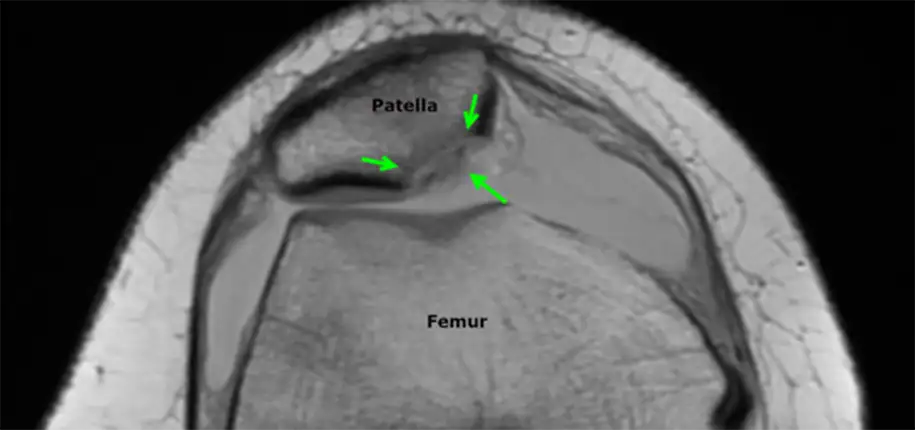

The diagnosis is typically made by history and physical examination. Knee x-rays are obtained initially to look for bone injuries, but cannot fully show the extent of soft tissue damage. For this reason, an MRI is performed soon after to assess the ligaments and cartilage and help determine whether surgery will be necessary. The MRI will also show underlying anatomical features that may predispose to the instability of the patella. If there is a significant injury to the cartilage covering the bone, a loose fragment in the joint, or tearing of the main ligament that stabilizes the patella, surgical treatment is recommended.

Luckily for Patrick Mahomes, the MRI did not show damage to the cartilage or ligaments. He was treated medically with physical therapy and able to return to play in a couple of weeks. The child with the MRI below was not as fortunate and required surgery to repair the patella. After a patellar dislocation, there is an increased risk of a recurrent dislocation, so continued follow-up and therapy are necessary.